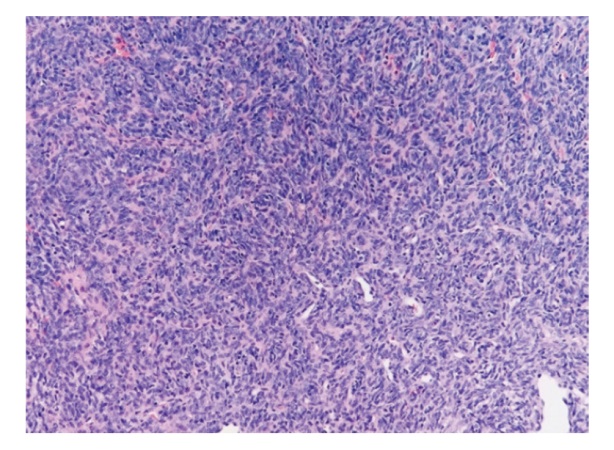

治疗头颈部软组织肉瘤对于完整切除和功能保护有较高的挑战。现报道1例声门上区喉滑膜肉瘤患者的诊疗经过,并就相关文献进行复习,以提高对该类疾病的认识。